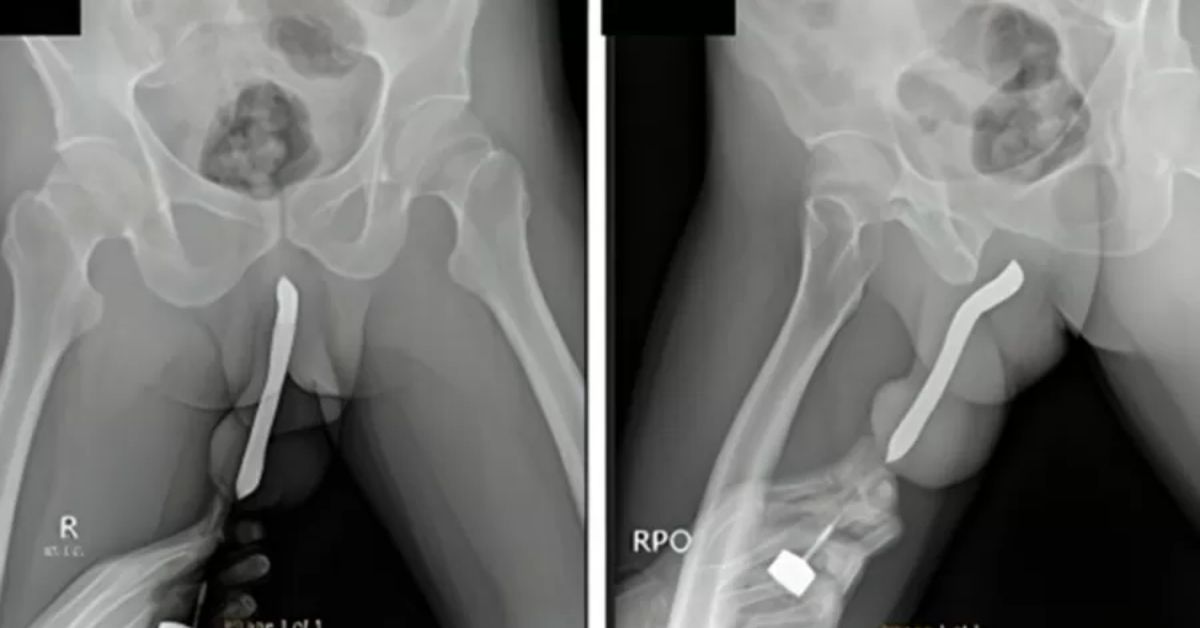

Homem vai parar no hospital por motivo inusitado; objeto quebrou